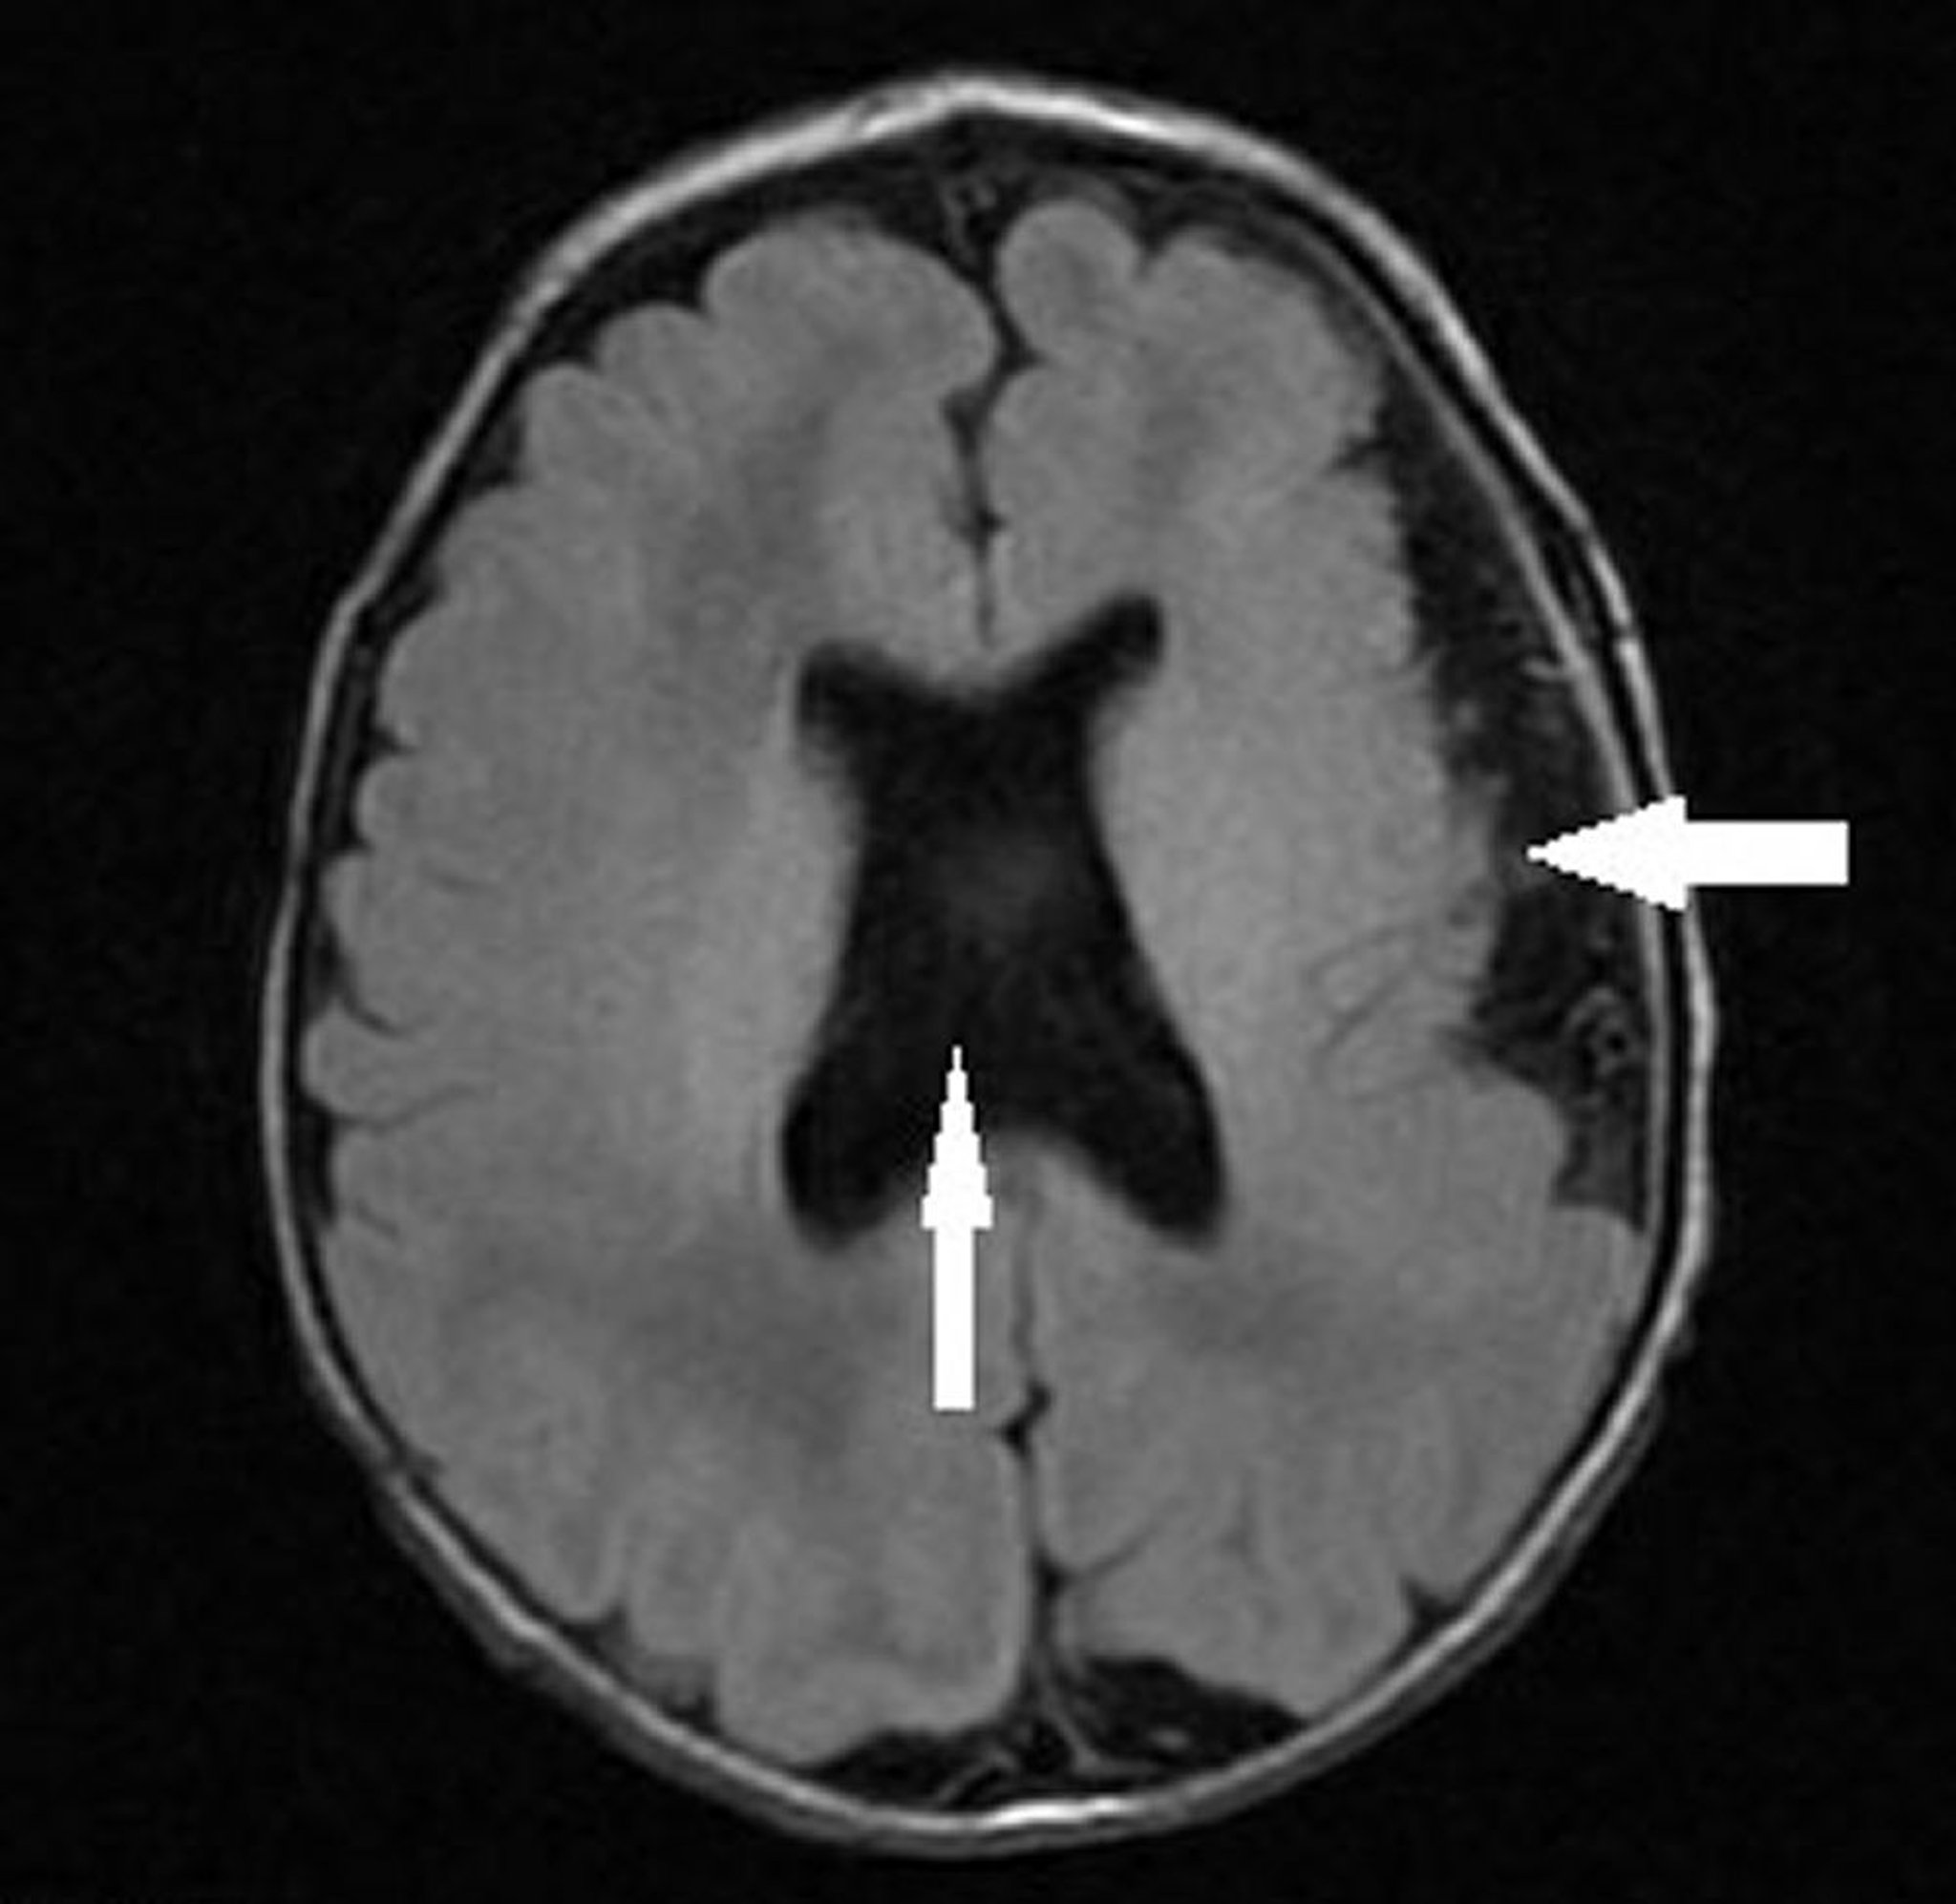

Полимикрогирия со септооптической дисплазией

На данном изображении показан грудной ребенок с полимикрогирией левого полушария (стрелка влево), отсутствием прозрачной перегородкой и аномальной конфигурацией желудочков (вертикальная стрелка), что соответствует септо-оптической дисплазии (гипоплазия зрительного нерва, отсутствующая или аномальная прозрачная перегородка и гипоплазия гипофиза).

Image courtesy of Stephen J. Falchek, MD.